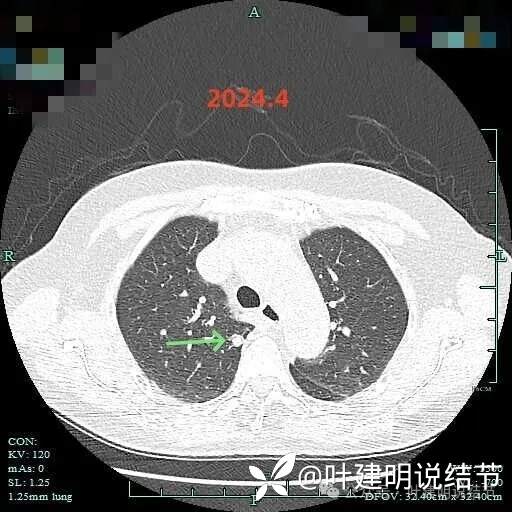

2024年4月右下病灶血管进入明显,整体密度显高,表面稍不平,欠光滑。

右上实性结节密度高,无显著进展,表面相对较光滑。